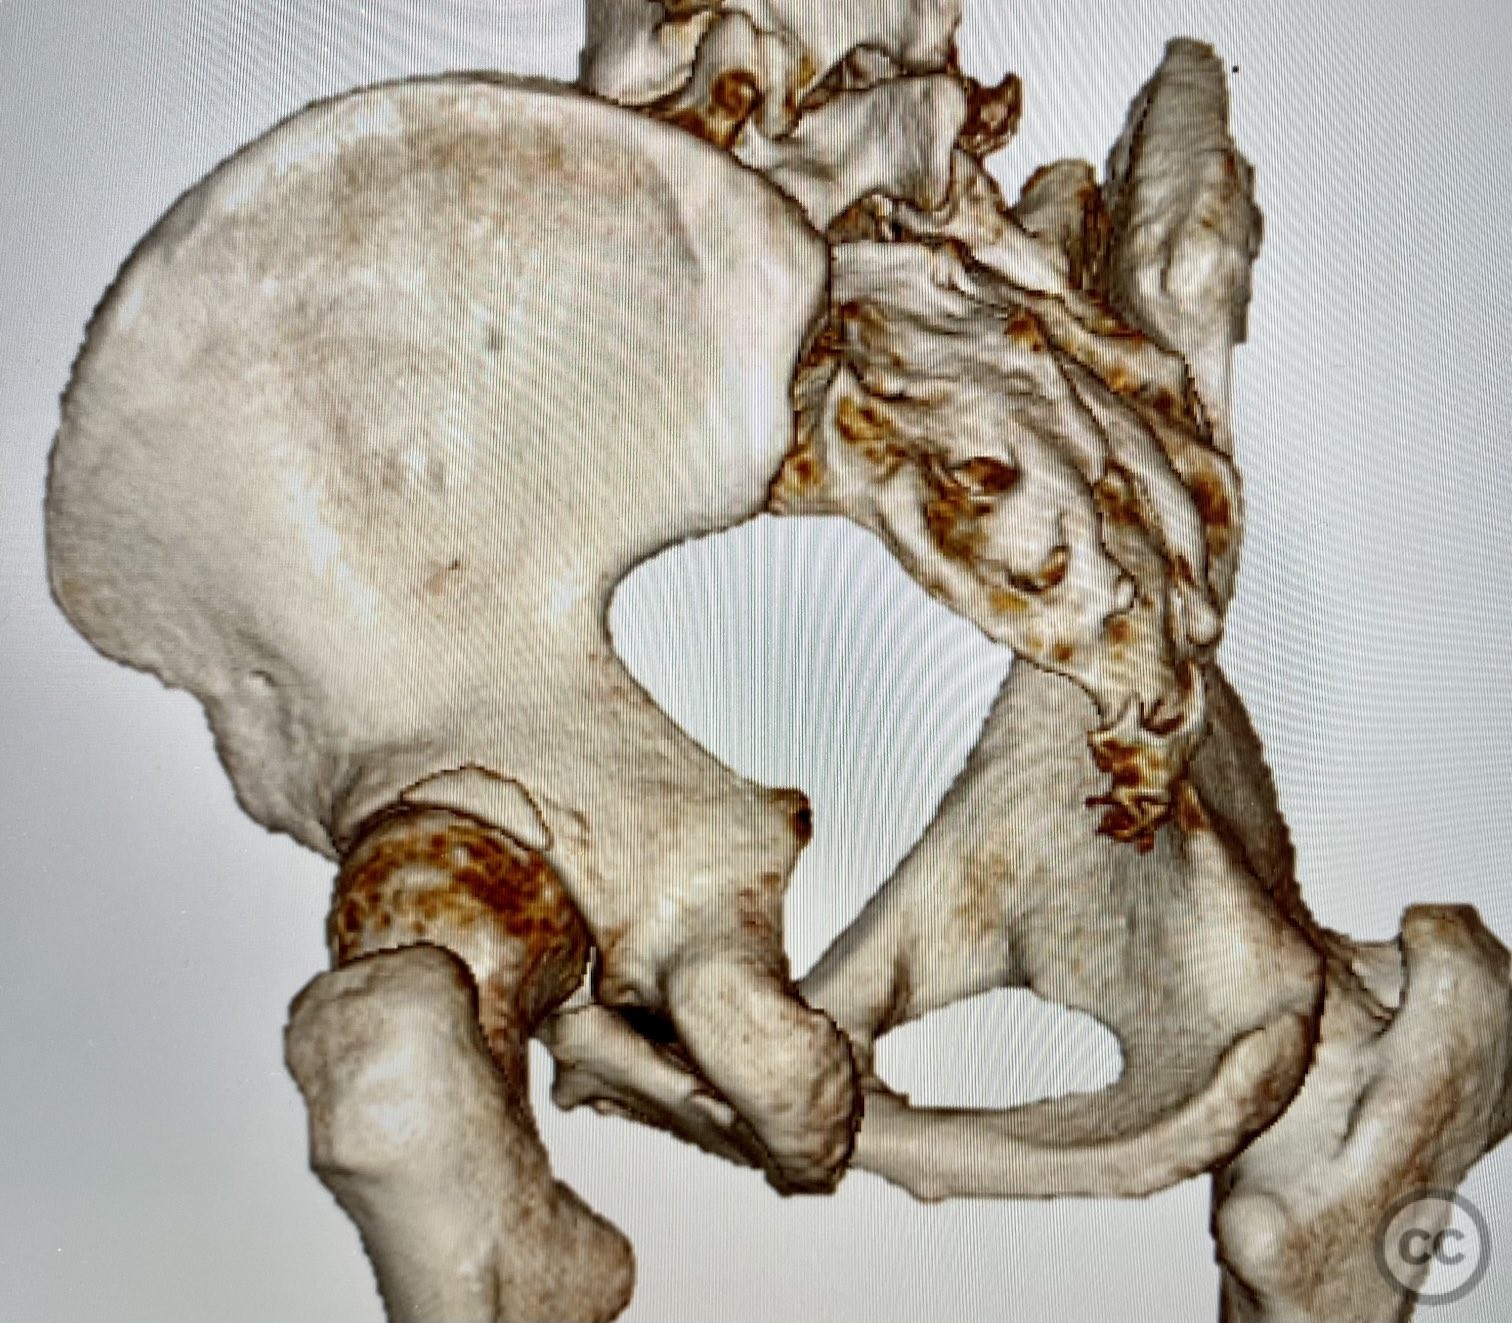

Clinical and radiological findings:  A patient involved in a motor vehicle collision presented with left hip pain exacerbated by any attempted movement. Initial axial and surface-rendered computed tomography (CT) imaging demonstrated an essentially nondisplaced posterior wall (PW) acetabular fracture (AO/OTA 62-A1.1). However, the anteroposterior (AP) scan image and coronal reconstructions revealed significant hip joint asymmetry. Examination under anesthesia with fluoroscopic guidance confirmed persistent joint incongruity, with the femoral head subluxating posteriorly at 50–60 degrees of flexion. A pure chondral fragment was identified as being interposed between the femoral head and the intact region of the posterior wall, accounting for the clinical and radiological asymmetry.

Intraoperatively, persistent hip joint asymmetry was noted on fluoroscopic imaging, correlating with preoperative findings. The femoral head exhibited posterior subluxation at moderate flexion angles due to mechanical obstruction by a pure chondral fragment wedged between the femoral head and posterior wall. Removal of this fragment restored joint congruity and symmetry. The posterior wall fracture, though minimally displaced, was deemed unstable based on intraoperative assessment and fluoroscopic stress testing. The fragment’s capsular attachment facilitated stabilization using suture anchor repair. The use of a Kocher-Langenbeck approach was considered essential for adequate exposure, reduction, and stabilization; arthroscopic techniques were not employed.